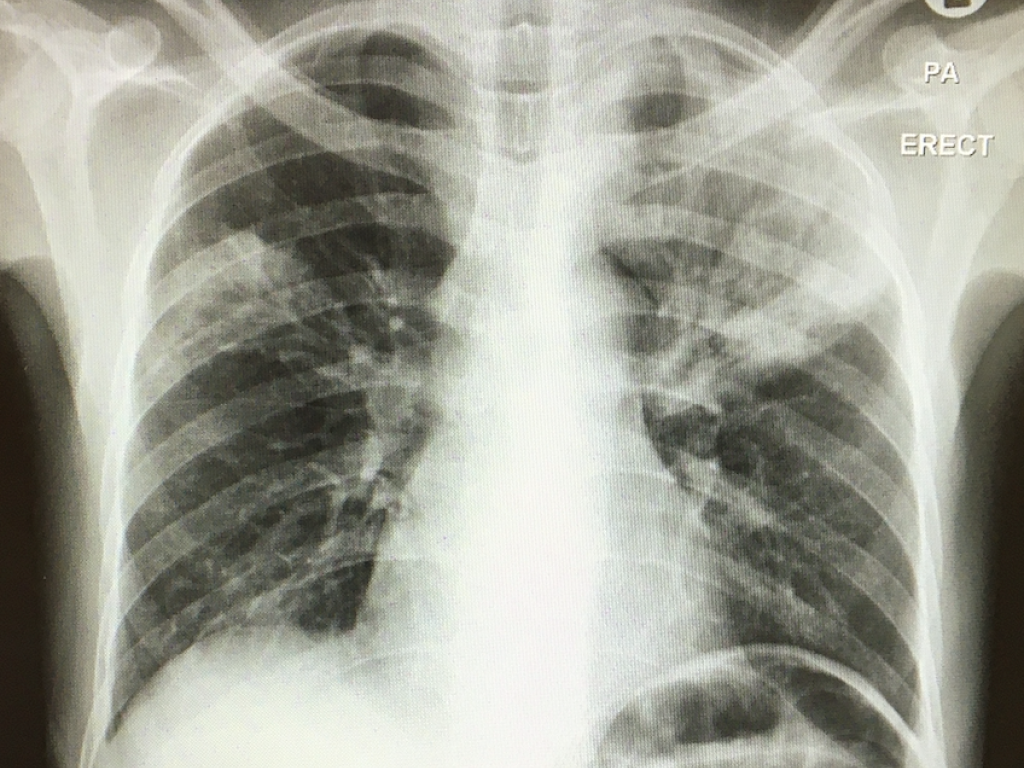

To begin addressing this problem, the team collected clinical details, chest X-rays, sputum, urine, and blood samples from participants at Khayelitsha Hospital, Cape Town. The patients received standard in-hospital care and follow-up. The study team checked the vital status of the patients at 12 weeks.

One hundred and twenty four of the 576 participants (22%) died within twelve weeks and 37% of these deaths occurred within a week of study enrolment.